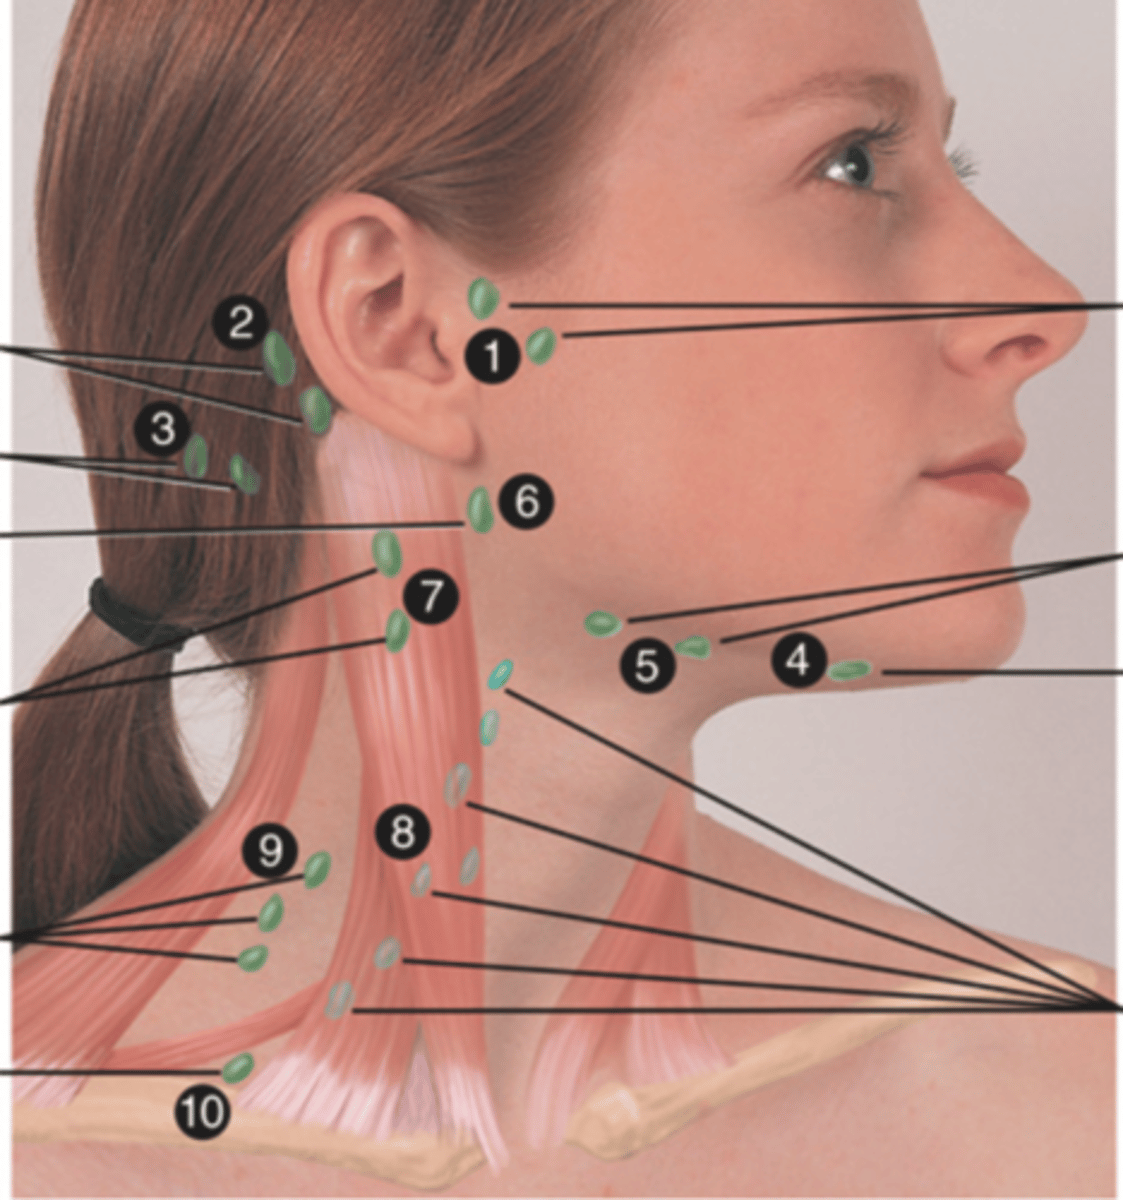

Major Lymph Nodes in the Neck (FUN!)

(Party People Often Sell Sardines Just So Dogs Pee Silver)

Preauricular Lymph Node

Lymph node in front of the ear (1)

Posterior Auricular Lymph Node

Lymph node behind the ear (2)

Occipital Lymph Node

Lymph node at the base of skull (3)

Submental Lymph Node

Lymph node under the chin (4)

Submandibular Lymph Node

Lymph node along base of mandible (5)

Jugulodigastric (Tonsil) Lymph Node

Lymph node under the angle of the mandible (6)

Superficial Cervical Lymph Node

Lymph node overlying the sternomastoid muscle (7); can feel enlarged even when there are no problems

Deep Cervical Chain Lymph Node

Lymph node located on the posterior triangle of the neck (8)

Posterior Cervical Lymph Node

Lymph node in the posterior triangle along the edge of the trapezius muscle (9)

Supraclavicular Lymph Node

Lymph node just above and behind the clavicle, at the sternomastoid muscle (10)